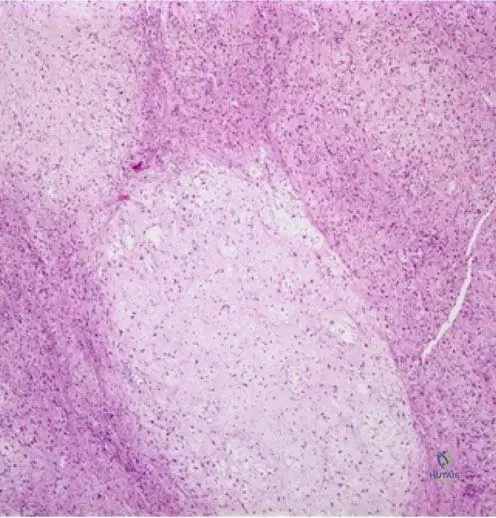

Rationale: The clinical text accompanying Fig. 8.106b states, "Higher power view (b) of primary lymphoma of bone. Note the round or oval appearing nuclei, which appear vesicular, owing to the margination of chromatin at the nuclear membrane. Nucleoli may be single and central, or may number two or three and be located adjacent to the nuclear membrane." This description is specific to lymphoma cells. Chondroblastic cells, osteoblastic cells, and fibroblasts have distinct nuclear and cytoplasmic features. Giant cell tumor stromal cells have oval nuclei but lack the specific chromatin margination described.

A pathologist is reviewing a biopsy specimen from a suspected primary bone lymphoma in a 50-year-old patient. On higher power magnification, the nuclei are described as round or oval, vesicular, with margination of chromatin at the nuclear membrane. Nucleoli are single and central, or two to three and located adjacent to the nuclear membrane.

Rationale: The description provided in the vignette and Fig. 8.106 refers to the characteristic nuclear features of the neoplastic lymphocytes found in lymphoma. The text states, "Note the round or oval appearing nuclei, which appear vesicular, owing to the margination of chromatin at the nuclear membrane. Nucleoli may be single and central, or may number two or three and be located adjacent to the nuclear membrane." These are features of the malignant B-cells. Osteoblasts, chondrocytes, fibroblasts, and adipocytes have distinct morphological characteristics.